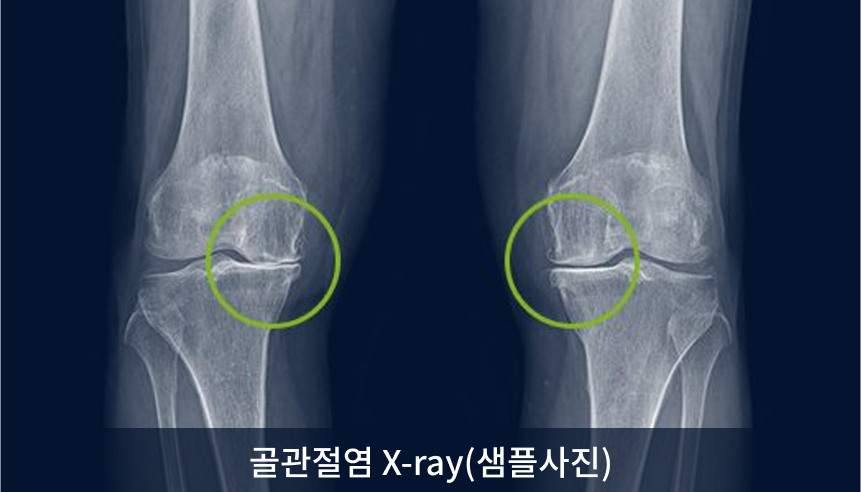

골관절염

골관절염은 관절의 가장 흔한 형태로 주로 뼈의 관절면을 감싸고 있는 관절 연골이 마모되어 연골 밑의 뼈가 노출되고

관절 주변의 활액막에 염증이 발생해 통증과 변형이 발생하는 질환입니다.

관절 연골은 자체 재생능력이 거의 없습니다.

발병률이 높고 관절 기능이 점점 줄어들기 때문에 빠른 대응이 필요합니다

골관절염은 관절의 가장 흔한 형태로 주로 뼈의 관절면을 감싸고 있는 관절 연골이 마모되어 연골 밑의 뼈가 노출되고 관절 주변의 활액막에 염증이 발생해 통증과 변형이 발생하는 질환입니다.

관절 연골은 자체 재생 능력이 거의 없습니다.

발병률이 높고 관절 기능이 점점 줄어들기 때문에 빠른 대응이 필요합니다.